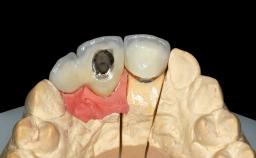

| Retention | Cemented, with prosthesis margin < 3mm submucosal Cemented, with prosthesis margin < 3mm submucosal |

| Provisional Implant-Supported Prosthesis | Prosthodontic margin < 3 mm apical to mucosal crest Prosthodontic margin < 3 mm apical to mucosal crest |